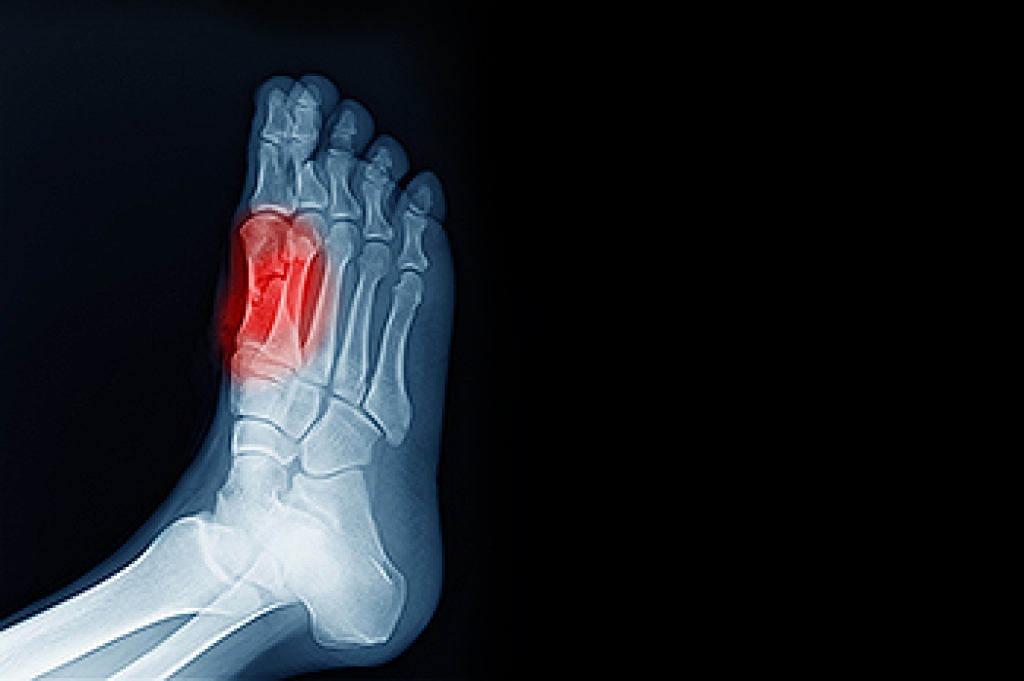

Sesamoiditis is a condition of the foot that affects the ball of the foot. It is more common in younger people than it is in older people. It can also occur with people who have begun a new exercise program, since their bodies are adjusting to the new physical regimen. Pain may also be caused by the inflammation of tendons surrounding the bones. It is important to seek treatment in its early stages because if you ignore the pain, this condition can lead to more serious problems such as severe irritation and bone fractures.

Sesamoiditis is inflammation of the small sesamoid bones located beneath the big toe joint. These tiny bones help absorb impact and aid in movement, but they can become irritated from repetitive stress. Common causes include activities that place pressure on the forefoot, such as running, dancing, or wearing high heels. Risk factors involve high arches, sudden increase in activity, and improper footwear. Symptoms often include pain beneath the big toe, swelling, and difficulty bending the toe. A podiatrist can diagnose sesamoiditis with a thorough exam and imaging, then recommend treatments such as medication, custom orthotics, and footwear changes. If you experience persistent toe joint pain, it is suggested that you visit a podiatrist to relieve discomfort and restore function.

Sesamoiditis is an unpleasant foot condition characterized by pain in the balls of the feet. If you think you’re struggling with sesamoiditis, contact one of our podiatrists of DM Foot & Ankle Associates . Our doctors will treat your condition thoroughly and effectively.